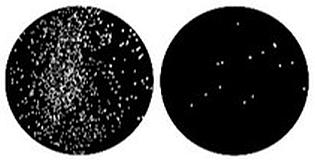

"We found that using nanomolar concentrations and a weak light source was enough to kill 92 percent of these multidrug-resistant superbugs, which had been resistant to all the clinical antibiotics we tested in our lab," Nagpal said.

"Only eight percent of bacteria survived from the original culture, which clearly demonstrates the strong efficacy and bactericidal action of the therapy. Since we had selected the worst bacterial strains with extremely strong antibiotic resistance to up to 20 different antibiotics, this represents a giant leap forward, especially considering the lack of available therapies."